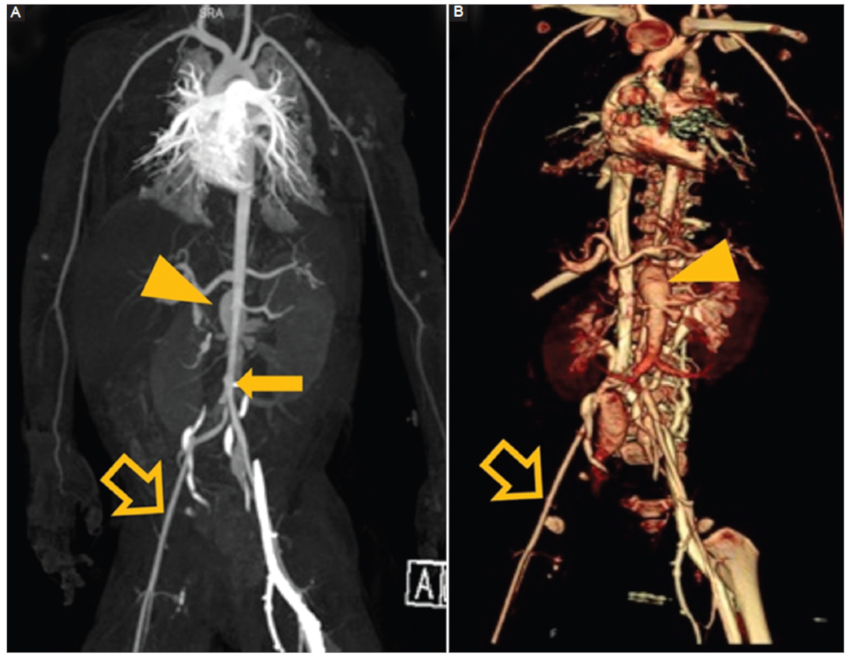

Fibrosis retroperitoneal

Proliferación de tejido fibro-inflamatorio que rodea la aorta abdominal y arterias ilíacas y con extensión hacia el retroperitoneo comprometiendo estructuras vecinas (vena cava inferior, uréteres, etc.) generalmente de origen idiopático, estableciéndose también la asociación al uso de fármacos, algunas neoplasias, infecciones, enfermedad por IgG4 y cirugías previas13. Destaca la presencia de un tejido periaórtico irregular con densidad de partes blandas que no compromete la pared posterior de la aorta (Fig. 8), que presenta realce con el contraste intravenoso y que en RM presenta señal baja ponderada en T1 con intensidad variable en imágenes ponderadas T2, que refleja el grado de inflamación activa14. En etapa aguda podemos observar compromiso del tejido graso regional y realce más ávido del contraste que en etapas crónicas (Fig. 9).

Fibrosis retroperitoneal. Hombre de 42 años con dolor abdominal. TC con contraste, cortes axiales. A: fase sin contraste. B-D: fase porto-venosa. Engrosamiento inflamatorio con densidad de tejido de partes blandas de contornos irregulares que rodea la cara anterolateral de la aorta abdominal infrarrenal (flecha), sin comprometer su pared posterior (flecha hueca). Este tejido realza con el contraste y se asocia a cambios inflamatorios del tejido adiposo adyacente. C y D: se observa extensión de este tejido a ambas arterias ilíacas comunes (punta de flecha).

Figura 8